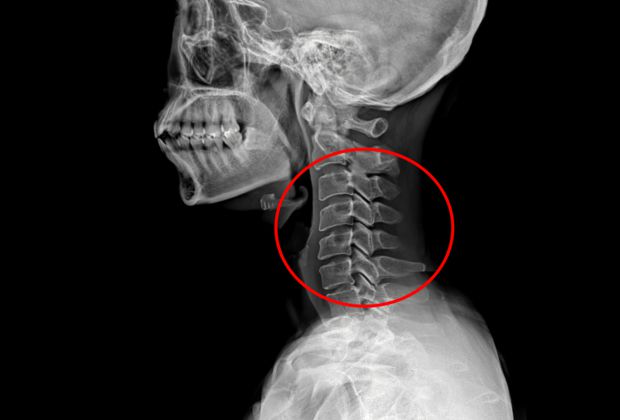

목 디스크 수술 환자에 대한 사후 처치를 제대로 하지 않아 환자를 숨지게 한 혐의로 재판에 넘겨진 신경외과 전문의에게 벌금형이 선고됐다.

A씨는 지난 2021년 6월 21일 인천의 한 병원에서 환자 B씨(60)의 목 디스크 수술을 집도한 뒤, 수술 부위에 발생한 혈종을 확인·제거하는 등 필요한 조치를 하지 않아 환자를 숨지게 한 혐의로 기소됐다.

목 디스크 수술은 수술 직후 혈압 상승이나 지혈 매듭 이탈 등으로 수술 부위에 혈종이 생길 가능성이 높은 것으로 알려져 있다. 이에 수술 후 엑스레이(X-ray) 검사를 실시하고, 혈종이 확인되면 제거해 기도 압박을 해소하는 등의 조치가 필요하다.

그러나 A씨는 수술 당일 회진을 마친 뒤 엑스레이 검사 결과를 확인하지 않은 채 오후 6시 3분께 퇴근한 것으로 조사됐다. 간호사가 촬영한 엑스레이 영상에는 혈종과 출혈이 나타났지만, A씨는 이를 확인하지 않았고 이후에도 검사 결과를 요청하거나 확인하지 않은 것으로 드러났다.